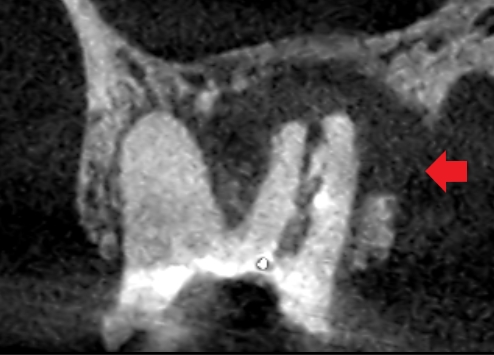

初診時の上顎第一大臼歯冠状断のCT画像です。

根の周りにできている膿の大きさは、舌側の歯槽骨を破って歯肉に到達するほどの大きさでした(矢印のところ)。